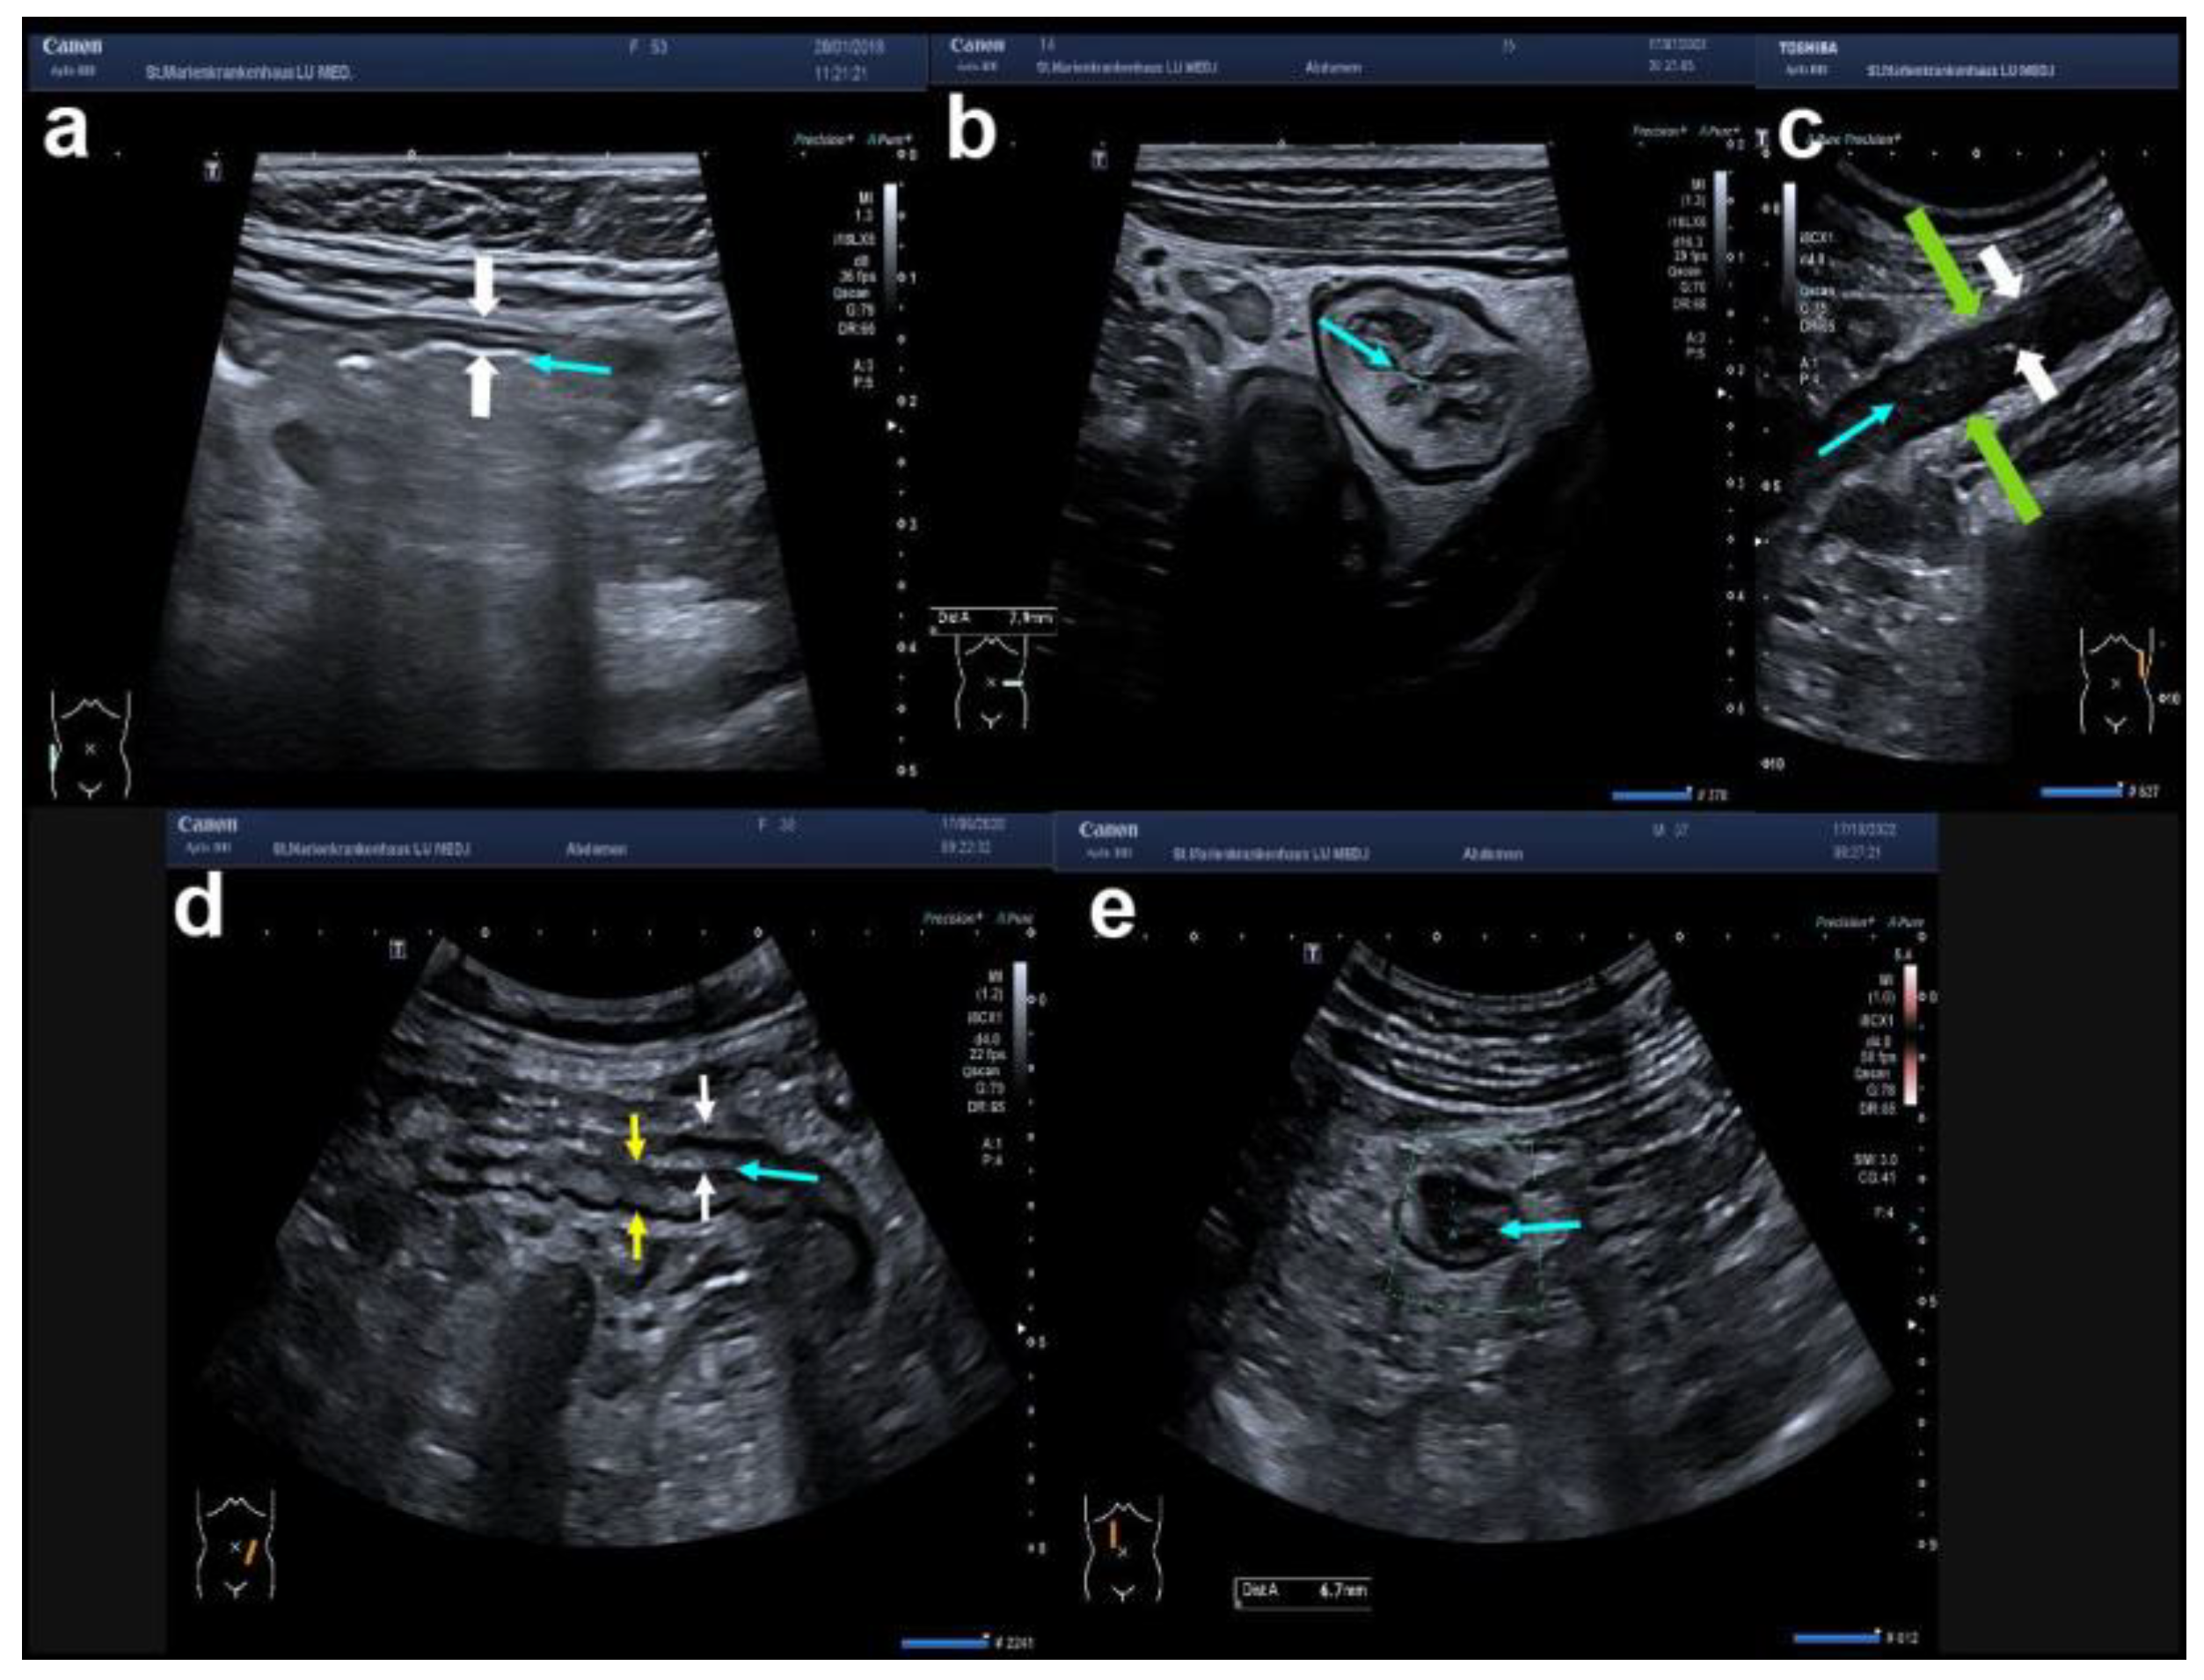

| Bowel wall | Bowel wall thickness (BWT) | [in mm (>3 mm without increased vascularity: Limberg 1)] | |

| Bowel wall stratification (BWS) | [preserved stratification; blurred stratification; localised loss of stratification; generalised loss of stratification] | ||

| Submucosal spiculates | [present; absent] | ||

| colour Doppler signal (CDS) | vascularity | [normal; increased within the wall (dots, Limberg 2); increased within the wall (streaks, Limberg 3); increased within the wall extending into the surrounding mesentery (streaks, Limberg 4)] | |

| Surrounding | Peri-intestinal fat (creeping fat) | (inflammatory fat or iFAT) | [normal; slightly increased hyperechoic tissue; markedly increased hyperechoic tissue] |

| abscess (hypoechoic area, no CDS) | [present; absent] | ||

| fistula (hypoechoic tract) | [present; absent] | ||